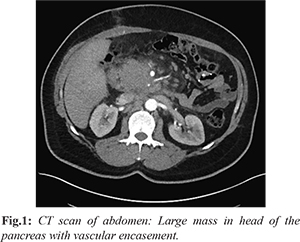

A 21-year-young man presented with painless jaundice, dyspnea and dry cough for 10 days. He reported significant weight loss over last one month. Laboratory tests showed mild elevation of total bilirubin and slight increase in transaminase and alkaline phosphatase, 135 U/L (normal 40-120 U/L). Serum CA-19.9 and CEA were normal. Contrast enhanced CT scan of abdomen revealed a large 6.6×4.3×3.5 cm ill-defined solid hypo-enhancing mass in the pancreatic head encasing the common hepatic artery, gastroduodenal artery and partly encasing main portal vein [Fig.1]. There was loss of fat planes between the mass and periportal soft tissue mass. Additional findings were hepatomegaly and mild bilateral pleural effusion. An endoscopic ultrasound (EUS) guided biopsy was performed using 22 G core needle (Acquire, Boston Scientific) via duodenum from the pancreatic mass. Microscopy showed a cellular neoplasm composed of non-cohesive, pleomorphic, and bizarre cells without any glandular formation [Fig.2a]. Cells were round-to-oval with vesicular to hyperchromatic nuclei, inconspicuous nucleolus and scant to moderate cytoplasm. The cells show marked atypia. There were occasional multinucleated giant cells. There were no lympho-vascular emboli, or perineural invasion spindle cells, sarcomatoid or osteoid changes [Fig.2b-d]. The surrounding fibrous stroma was scant (in contrast to conventional invasive pancreatic ductal adenocarcinoma). No transition between adenocarcinoma and undifferentiated components was observed. Immunohistochemically, most neoplastic cells were positive for IMP3 [Fig.3a].  IHC for mCEA, EMA and pancytokeratin were negative. Other markers like synaptophysin, chromogranin, CD 56, CD20, LCA, CD30, SALL4, s-100, HMB-45 and CA 19-9 were also negative in the tumor cells ruling out several differential diagnoses like neuroendocrine tumor, lymphoma, germ cell tumor and melanoma. Focal macrophages showed immuno-reactive for LCA and CD68 [Fig.3b,c]. The final diagnosis was an undifferentiated carcinoma of the pancreas. Due to logistic limitations ancillary techniques like ex vivo chemo sensitivity or next generation-based mutation analysis was not done in this case

UCP is more common in elderly age patients. The average age is 63-70 years with both genders being affected equally [6]. The common symptoms reported are abdominal or back pain (in two-thirds), painless jaundice (in one-third) and half the cases show weight loss [6,9]. Elevated serum CA19-9 levels are seen in two-third cases [6]. UCP is invasive cancer and carries a poor prognosis. In our case, patient was a 21 yr old male and presented with painless jaundice, dyspnea and weight loss with normal CA19-9 levels. Commonly UCP occurs in the body and tail of the pancreas (50-70%) [6,9]. The index case presented as a large ill-defined mass in the head of pancreas. The mass lesion was solid, hypo-enhancing and had loss of fat planes while others observed heterogeneous mass with hyper and hypoechoic regions [1].